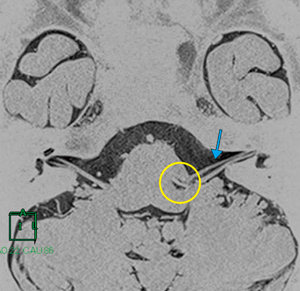

■症例1:脳動脈瘤頸部クリッピング術(70歳代,女性)

MRAにて,左内頸動脈後交通動脈(IC-PC)分岐部に未破裂脳動脈瘤を認めた。脳動脈瘤と動眼神経との位置関係を確認することを目的として画像を作成した。MRA像とHeavy T2強調画像は,撮像日および撮像位置が異なったため,Fusion機能で自動位置合わせを行った。これにより,元画像では把握が困難な血管の走行も立体的に把握できた(図2)。動脈瘤と動眼神経の位置関係を3Dで把握することにより,神経への手技的トラブルを避けることができ,脳動脈瘤頸部クリッピング術前シミュレーションとして有用な画像であった(図3)。

図2 症例1:Heavy T2強調のMPR再構成画像と脳神経Multi Volume画像の比較 |

図3 症例1:脳神経Multi Volume画像 |